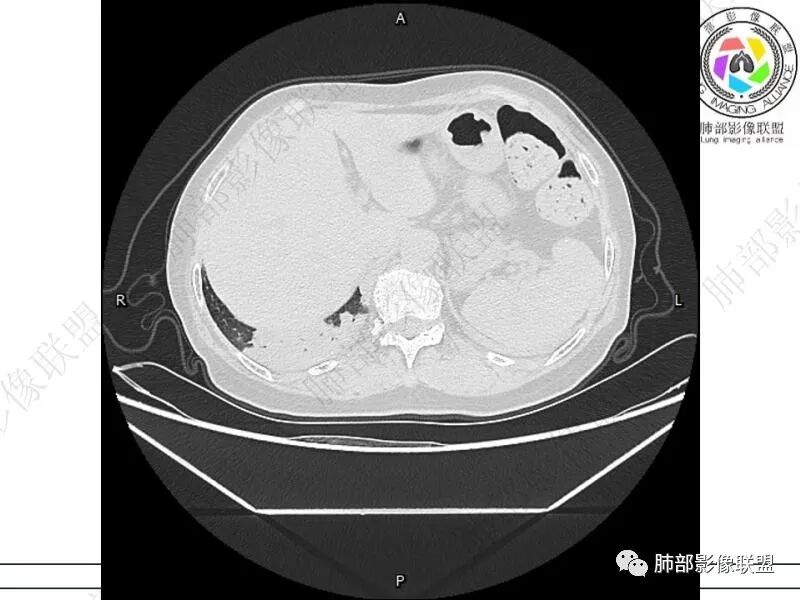

摘星空竹子:两肺胸膜下多发实性结节、磨玻璃影及实变影,短期复查病变有所进展,考虑感染性病变,隐球菌可能,患者有右半结肠癌手术史,转移不能除外。

简单:双肺及胸膜下多发小结节,双下肺胸膜下宽基底团块影,短期内病灶进展考虑炎性病变,隐球?患者ca术后,双肺小结节随诊除外转移

songml:老年女性,结肠癌术后,下腹隐痛。双肺胸膜下散在结节影,大小不一,下肺为著,肺野清晰,实变结节有强化,有毛毛征。考虑隐球菌感染。

老年女性,结肠癌术后。两下肺胸膜下为主片状实变,右下肺短期复查融合且病灶长轴平行于胸膜,实变内可见支气管充气征,边缘磨玻璃晕,另两肺内胸膜下散在数枚小结节状、楔形实性灶。考虑感染性病变,隐球菌可能,鉴别肺转移。

1.老年男性,肠癌术后低热,低免疫状态。C反应蛋白升高,隐球菌荚膜抗原检测阴性。

2.影像特征:双肺胸膜下多发实性结节、磨玻璃影及实变影,胸膜下优势分布、晕征、胸膜下脂肪间隙存在,部分病灶边界平直征,有侧向融合趋势。

3.CEA复查1.8ng/ml,常规情况,基本排除转移。广谱抗生素治疗后无效,病灶仍然进展,考虑特殊感染。